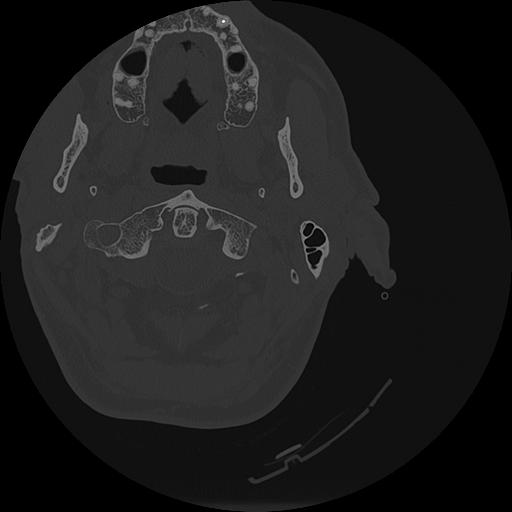

7 HUESO,,Vol,0.5,HUESO,,